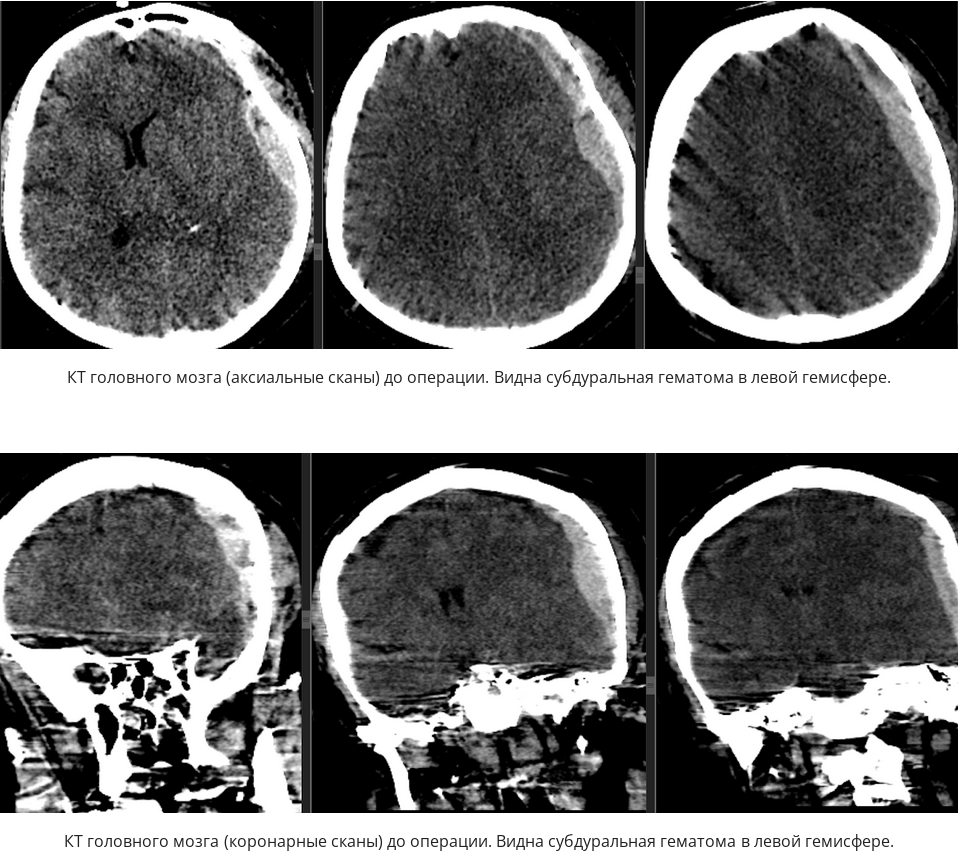

Инсульт удаление гематомы

Инсульт удаление гематомы 108 фотографий